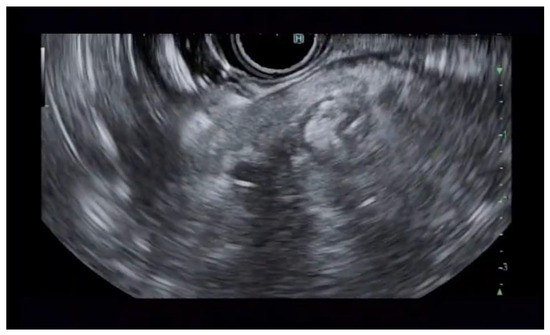

Additional notable cases in our series included a pancreatic cyst with a high-grade dysplastic nodule in an 80-year-old female patient. The initial 11.0 × 10.0 mm nodule was completely ablated (0.0 × 0.0 mm residual) after a single RFA session using a 19-gauge/7 mm needle at 50 watts of power for three applications with no complications (Figure 1, Figure 2 and Figure 3). Similarly, a 41-year-old male with a 13.5 × 8.5 mm insulinoma in the pancreatic neck who presented with multiple syncopal episodes secondary to hypoglycemia achieved complete radiologic and biochemical resolution after a single RFA session using a 19-gauge/5 mm needle at 10 watts of power for two applications (Figure 4, Figure 5 and Figure 6), with no adverse events and normalization of his insulin and glucose levels post-procedure and the resolution of his syncope.

Figure 2. Pancreatic cyst fluid aspiration prior to RFA.